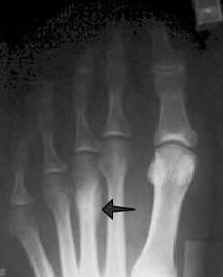

a metatarsal stress fracture.

Most stress fractures occur in the weight bearing bones of the foot and lower leg. The most commonly affected site is the second or third of the long bones (metatarsals) between the toes and the midfoot. Stress fractures also can occur in the heel, the outer bone of the lower leg (fibula) and the navicular, a bone on the top of the midfoot.